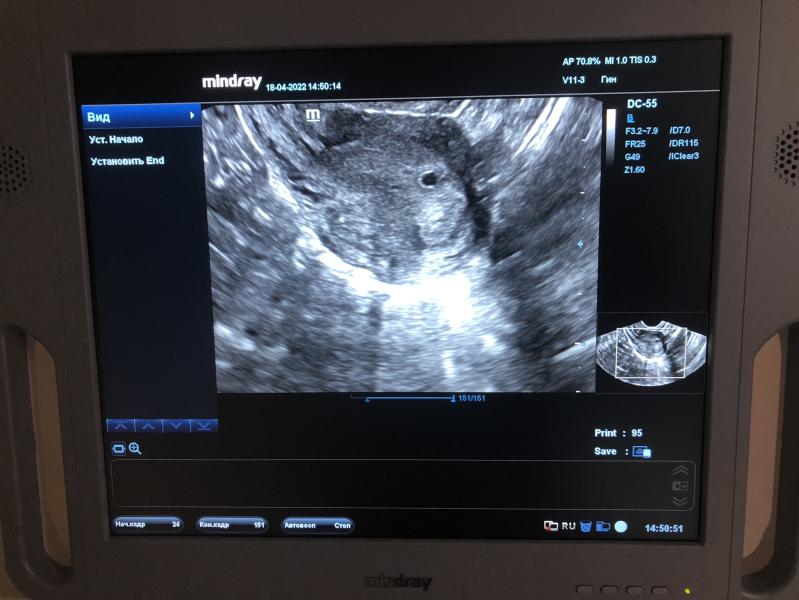

Подтвердили маточную беременность , 3 мм плодное яйцо ❤️🙏🏻

Только срок у меня 6 недель

Поставили 3-4 недели

Нормально если такое отставание?